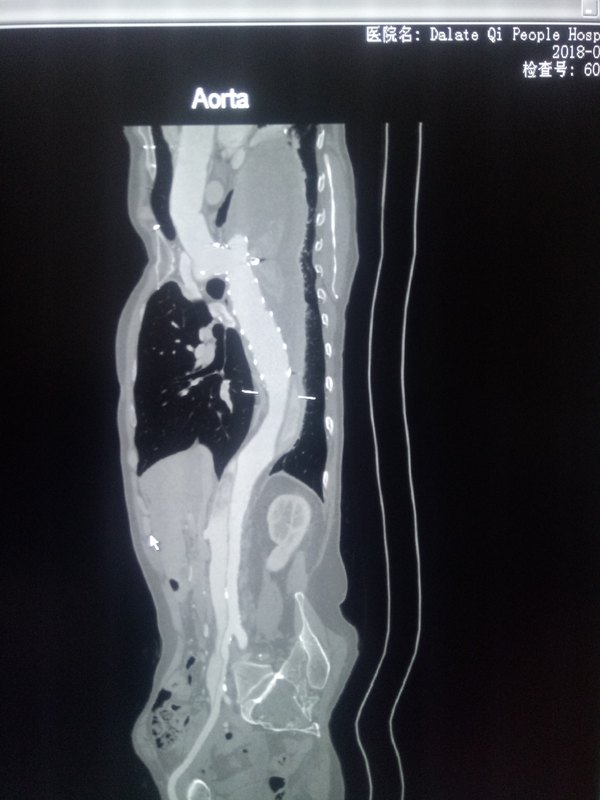

馬凡氏綜合癥的簡介、定義、臨床、診斷以及治療最近在影像診斷的時候遇到一例馬凡氏綜合癥病人,想在我休息的時候借助好醫(yī)生這個平臺和大家一起了解認識學習一下這個疾病。 馬凡氏綜合癥是一種令人惋惜的天才病,如不早發(fā)現(xiàn)診斷,并手術治療,往往都英年早逝。為什么說它是天才病,主要因為這樣的患者往往擁有異于常人的體格,好像這是上天賜給他們的禮物,領他們在各個領域發(fā)揮出色,可偏偏又早早的收回的這些異能人。像美國總統(tǒng)林肯,排球女將海曼等。 馬凡氏綜合癥我們影像科又給起了一個易記住的名字叫麻煩死綜合癥,因為在我們發(fā)現(xiàn)這種病寫報告麻煩才這樣起名。那么馬凡氏綜合癥的醫(yī)學定義是什么呢? 這里我來給大家說明,馬凡(ManFan)綜合癥為先天中胚層發(fā)育不良性疾病,長為長染色體顯性遺傳型結締組織病,長累及骨骼系統(tǒng),心血管系統(tǒng),以及眼部及中樞系統(tǒng)。優(yōu)以骨骼和血管最常見。而且絕大多數(shù)患者是死于心血管疾病的,主要是主動脈夾層破裂,心包壓塞,主動脈瓣關閉不全。這也是好多巨人們倒下的原因。 馬凡氏綜合癥的臨床表現(xiàn)。骨骼改變,1.身材瘦高,四肢細長。 2.蜘蛛指/趾樣改變。3.胸骨、脊柱畸形。 眼部改變,1.雙側晶狀體脫位或半脫位,2.視網(wǎng)膜剝離,虹膜震顫,白內障,斜視,瞳孔縮小,繼發(fā)性青光眼。 3.心血管改變,1.主動脈病變、夾層、壁增厚,破裂。2.主動脈瓣發(fā)育不全,二尖瓣脫垂,冠狀動脈受累,心臟增大,心率失常等。 診斷主要依據(jù)上述三點加有遺傳病史,還有一些診斷依據(jù)在這不在贅述。 治療主要是心血管系統(tǒng)及眼睛的預防治療?,F(xiàn)有專門最好的心血管治療方法,有意者請聯(lián)系我。注有紅十字會贊助。 檢查方法包括X線的骨骼細長指數(shù)測定。 CTA及MRI的心血管改變。 裂隙燈檢查晶狀體脫位。